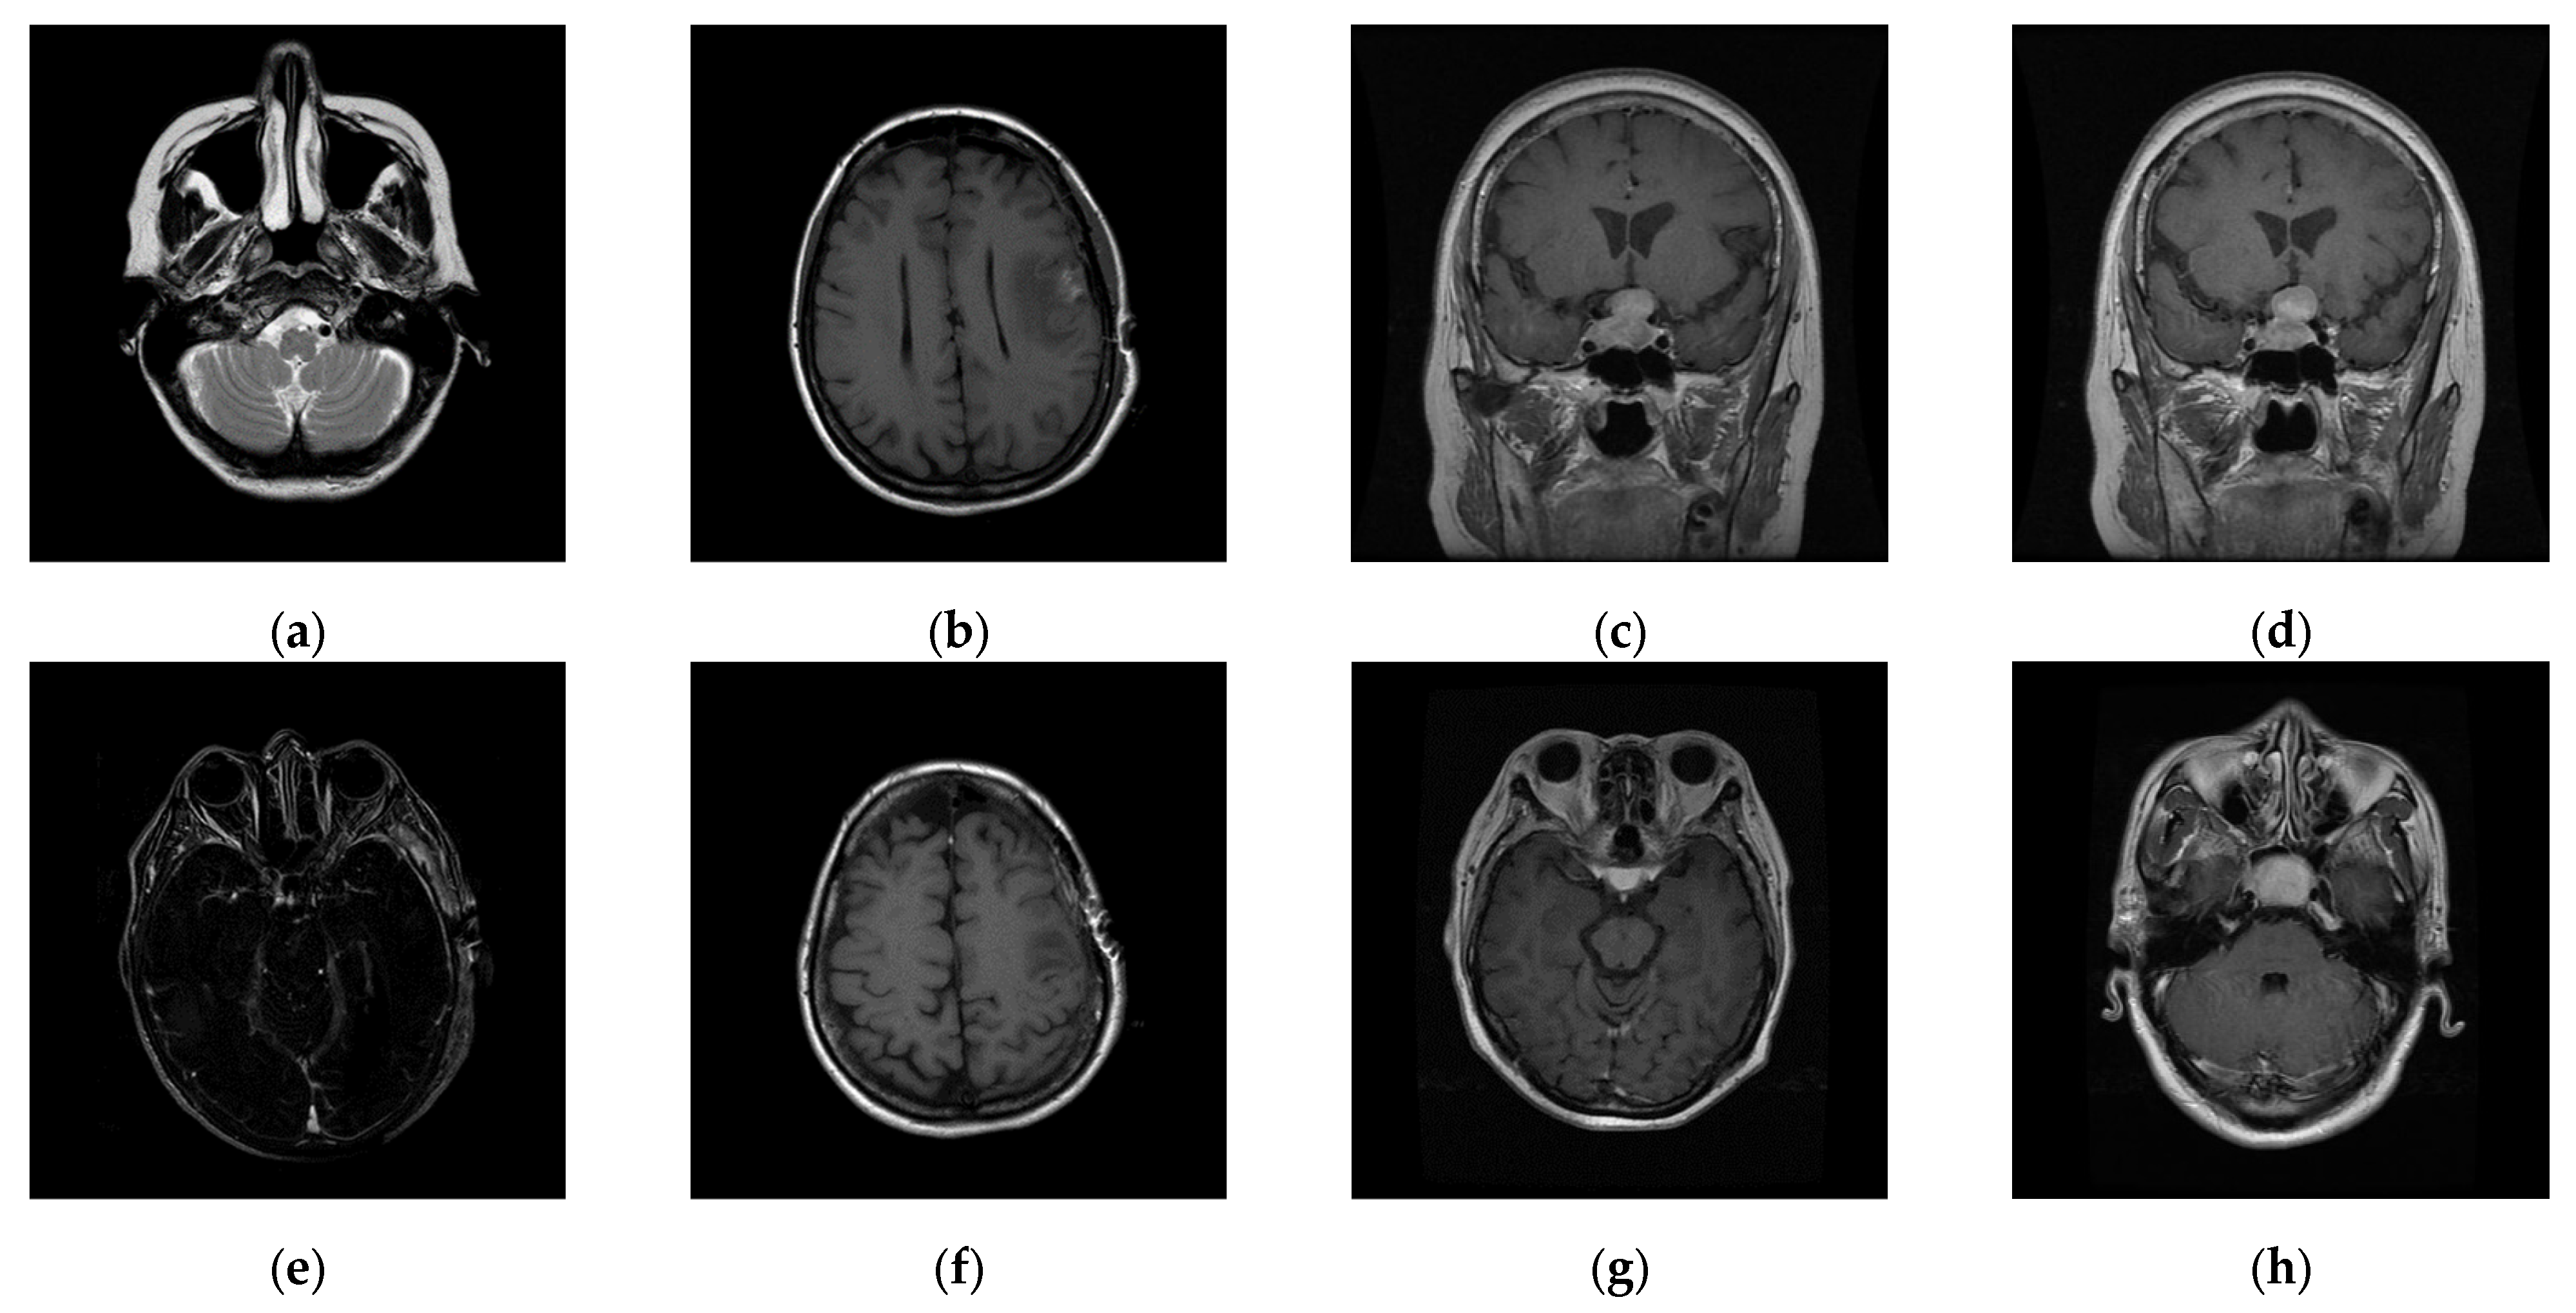

The experiments were conducted on two systems. The first system ran on Ubuntu 22.04, equipped with an Intel i7-9700KF CPU @ 3.60GHz (8 cores), an Nvidia GeForce RTX 3090 GPU, 32 GB of RAM, and Pytorch (https://pytorch.org/) for the experimentation. The second system, called the Type 1 device, is a notebook with an Intel(R) Core (TM) i7-10510U CPU @1.80 GHz 2.30 GHz, 16.0 GB RAM, 64-bit Windows operation system, and GPU MX 250. The third system, called the Type 2 device, is a notebook with an 11th Gen Intel(R) Core(TM) i5-11400H @ 2.70 GHz 2.69 GHz, 24.0 GB RAM, 64-bit Windows operation system, and GPU Nvidia GeForce 3060. The second system is a notebook that was released around 2019 or early 2020. The third system is also a notebook that was released in early 2021. The two systems were used to simulate resource-constrained environments. Different medical and test images were used as the test images to evaluate the performance of our proposed scheme and to make comparisons between our scheme and Qin et al.’s scheme [20]. In the first experiment, eight medical images, which are MRI scans of the brain, were randomly selected from the Osirix database [21] as test images and are presented in Figure 10 to demonstrate the performance of our proposed scheme in detail. In the second experiment, one hundred medical images, which are also MRI scans of the brain, were randomly selected from the Osirix database [21] to form Dataset 1 and Dataset 2, as shown in Figure 11, to prove the stable performance of our proposed scheme. In the third experiment, six general grayscale images, sized 512 × 512, demonstrated in Figure 12, were used to compare with those offered by Qin et al.’s scheme [20]. The logo depicted in Figure 13a was used as the watermark for the first and the second experiments and Figure 13b was used as the watermark for the third experiment.

Figure 10. Eight medical test images. (a) 10.png; (b) 11.png; (c) 14.png; (d) 16.png; (e) 19.png; (f) 26.png; (g) 31.png; (h) 57.png.